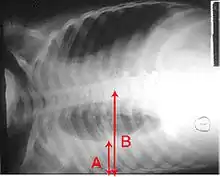

الأشعات

عادةً (في الوضع الطبيعي) لا يمكن رؤية الفراغ الموجود بين طبقتي الغشاء البِلُّوري: الغشاء البِلّوري الجداري (أي المُبَطّن للقفص الصدري) والغشاء البِلّوري الحشوي (أي الذي يغطي الرئة). والارتشاح البِلّوري يتسرب ليملأ الفراغ الموجود بين هاتين الطبقتين. وبما أن الارتشاح البِلّوري له كثافة مماثلة لسوائل الجسم (أو الماء)، فإنه من الممكن رؤيته من خلال صور الأشعات. وبما أن للارتشاح كثافة أعلى من كثافة بقية الرئة (حيث أن الرئة تحتوي على الهواء) فإنه ينجذب إلى الجزء السفلي من التجويف البِلّوري. يتصرف الارتشاح البِلّوري وفقا لديناميات السوائل الأساسية، متسقاً مع شكل الرئة وتجويف الصدر. وإذا كان التجويف البِلّوري يحتوي على كل من الهواء والسائل (hydropneumothorax)، فإن السائل سيكون له مستوى أفقي "fluid level" بدلاً من أن يتسق مع مساحة الرئة.[2] لأشعات الصدر المُلتَقَطة في الوضع الجانبي lateral decubitus position (أي مع وضع المريض على جانبه أثناء التقاط الأشعة) حساسية أكبر، ويمكنها الكشف عن وجود الارتشاح في حال وجود حتى اقل من 50 مل من السوائل. يلزم وجود 300 مل على الأقل من السوائل حتى يتسنى لأشعات الصدر في الوضع القائم (upright position) الكشف عن بعض علامات الارتشاح البِلّوري (على سبيل المثال، التحام الزاوية بين الضلوع والحجاب الحاجز costophrenic angle).